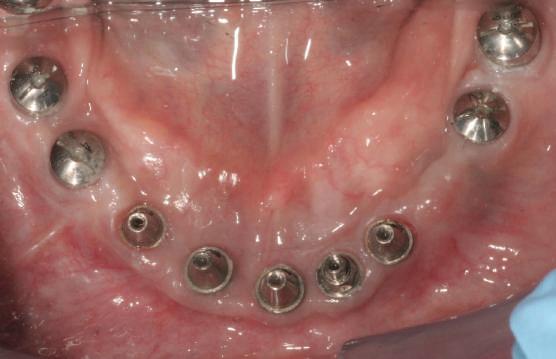

Cazul (3)

Refrezarea bonturilor individualizate

Pacientul prezenta dentiţie maxilară şi mandibulară eşuată datorită cariei secundare provocată de xerostomia post-iradiere. Pacientul suferise o disecţie cervicală radicală pentru înlăturarea carcinomului cu celule scuamoase la nivelul gâtului cu 9 ani înainte, urmată de radioterapie dar fără limită de ecranare. S-a utilizat o abordare stadializată pentru a evita protezele mobilizabile pe ţesuturile moi, extrem de uscate. Pacientul a optat pentru tratarea prioritară la nivel mandibular.

Fig. 9 prezintă bonturile de vindecare adiacente dinţilor naturali menţinuţi temporar, iar fig. 10 bonturile individualizate din prima etapă, inserate cu un contur gingival relativ bun şi fără recesie. Recesia era clar vizibilă în jurul tuturor bonturilor din prima etapă, după extracţiile adiacente şi plasarea implanturilor din a doua etapă (fig. 11). Atitudine: S-a decis îndepărtarea acestor bonturi şi amprenta corpului implantar al tuturor implanturilor astfel încât bonturile noi şi cele din prima etapă să fie frezate împreună pentru paralelism şi poziţionarea adecvată a marginii gingivale. Întrucât aceasta necesita îndepărtarea bonturilor din prima etapă care menţineau proteza provizorie, înainte de îndepărtarea tuturor bonturilor individualizate s-au plasat bonturi provizorii, cu scopul de a asigura poziţionarea adecvată şi dimensiunea verticală a restaurării provizorii. Aceste bonturi provizorii au menţinut apoi restaurarea temporară,

Cazul (3): Refrezarea bonturilor individualizate

Figurile

9. Bonturile de vindecare.

10. Bonturile individualizate în prima etapă.

11. Recesia evidentă în jurul bonturilor din prima etapă, după extracţiile adiacente şi inserarea implanturilor din faza a doua.

12. Bonturile refrezate şi noile bonturi individualizate.

în timp ce toate bonturile individualizate au fost fabricate şi/sau frezate în laborator. Fig. 12 prezintă plasarea bonturilor refrezate (la implanturile din prima etapă) şi bonturile individualizate noi (la cele din a doua etapă).